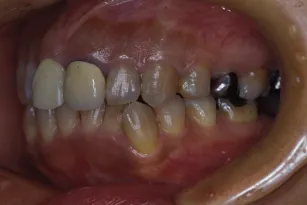

初診時

治療完了時

| 患者様のお悩み | 咀嚼障害、左の奥歯が抜けた。 |

| 治療法・使用素材 | インプラント治療の後、セラミック治療 |

| 患者様の年代 | 60代 |

| 治療開始年齢 | 60代 |

| 治療にかかった期間 | 1年6か月 |

| 性別 | 男性 |

| この治療のリスクについて | 歯ぎしりがひどいので修復物の耐久性が将来的に問題になる可能性があること |

| 治療にかかった費用 | 450万円 |